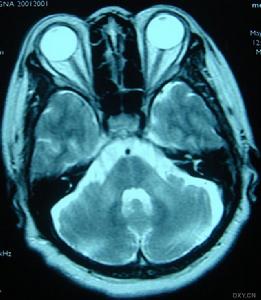

(4)輔助檢查:①X片可見脊柱和骨骼畸形;MRI可見脊髓變細;②心電圖常見T波倒置、心律失常和傳導阻滯,超聲心動圖示心室肥大,視覺誘發電位波幅下降;③DNA分析FRDA基因18號內含子GAA大於66次重複。

遺傳性共濟失調2、Friedreich型共濟失調(FRDA)X片可見脊柱和骨骼畸形;MRI可見脊髓變細;心電圖常見T波倒置、心律失常和傳導阻滯,超聲心動圖示心室肥大,視覺誘發電位波幅下降。